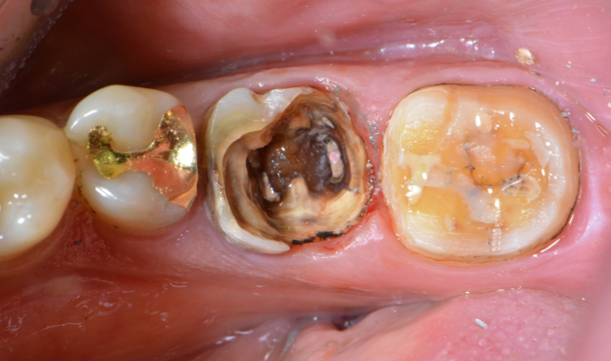

심한 우식 치아 크라운 수복

Before

가끔은 이 치아를 과연 살릴 수 있을까 싶은 정도로 많이 망가진 치아를 만나곤 합니다.

조금 무리해서라도 상한 치아를 레진으로 보강한 후 크라운 수복 하곤 합니다.

위 케이스는 정말 다행스럽게도 6년이 지나도록

잘 유지되고 있습니다.